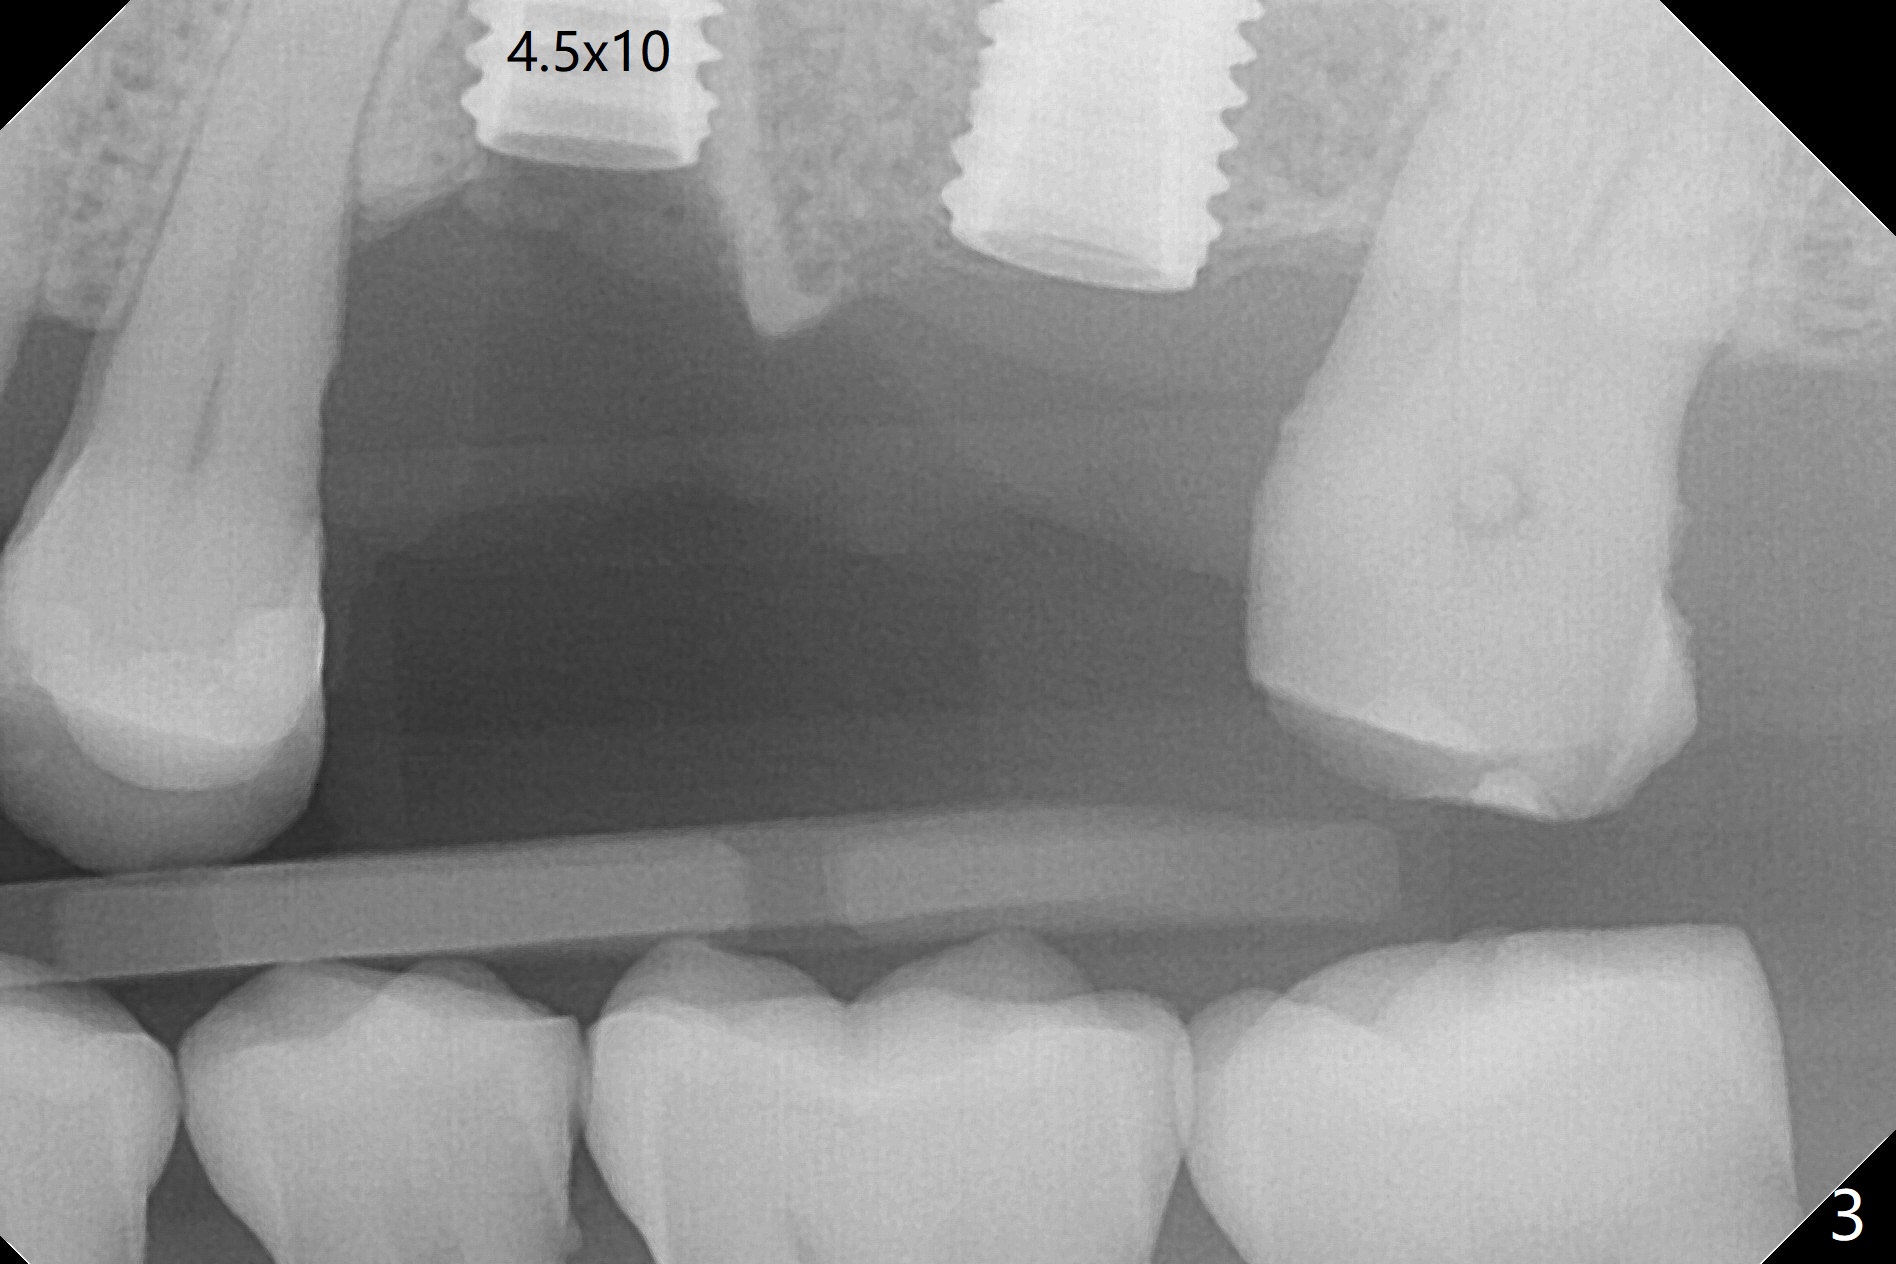

After extraction of the tooth #13 residual root, the bone in the distal wall of the socket looks white. Intraop PA rules out root structure (Fig.1 *). Osteotomy is conducted according to drill sequence. Bitewings are taken to check implant placement level (Fig.2,3). Following implant level adjustment and healing abutment installment (Fig.4,5 (*: bone graft)), the implant at #13 is found to be close the root of #12 (Fig.6 *), i.e., not parallel to the implant at #14. Introspectively, 2.2x10 mm drill seems to be long. When it touches the bone, the cylinder portion of the drill (Fig.7 red) does not engage into the sleeve (green). When it goes into the bone, it may have been deflected mesial due to the slope of the distal wall of the socket (hard bone, Fig.8 open arrow)). If a shorter drill (such as 2.2x7.3 or 8.5 mm) were used (Fig.9), the deflection would be minimal if drilling is slow (Fig.10). CT taken 1 week postop shows that the implant at #13 is approximately 1 mm near the root of the tooth #12, but the neurovascular bundle to the latter seems not to have been interrupted (Fig.11,12). The buccopalatal trajectory at #14 is within normal limit (Fig.11,13 (B: buccal)). There is no periapical radiolucency at #12 five months postop (Fig.14). However the cemented abutments are incompletely seated (<). The patient is reluctant to return for impression 17 months postop (due to coronavirus); with attention, the same abutment at #13 is reseated completely; an abutment with longer cuff and narrower diameter is also seated completely (Fig.15).